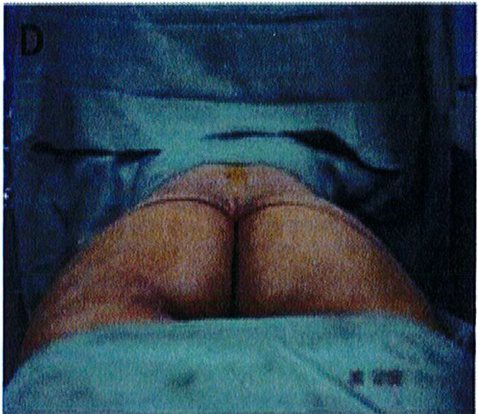

Kết quả phẫu thuật quan sát trên Hình. 3-5.

Hình. 3. (A-H) Tiền phẫu, chu phẫu và sau hậu phẫu 6 tháng của một bệnh nhân nữ 38 tuổi đươc ghép túi đôn mông với thể tích 330 cm3.

Hình. 4. (A-I) Hình ảnh tiền phẫu, chu phẫu và sau hậu phẫu 11 tháng của một phụ nữ 25 tuổi đã được thực hiện hút mỡ vùng éo, hông và sau xương vùng, đồng thời ghép khối cấy thể tích 270cm3.

Hình. 5. (A-F) Hình ảnh tiền phẫu và sau hậu phầu 4 tháng của bệnh nhân 67 tuổi, ghép khối implant thể tích 300 cm3.